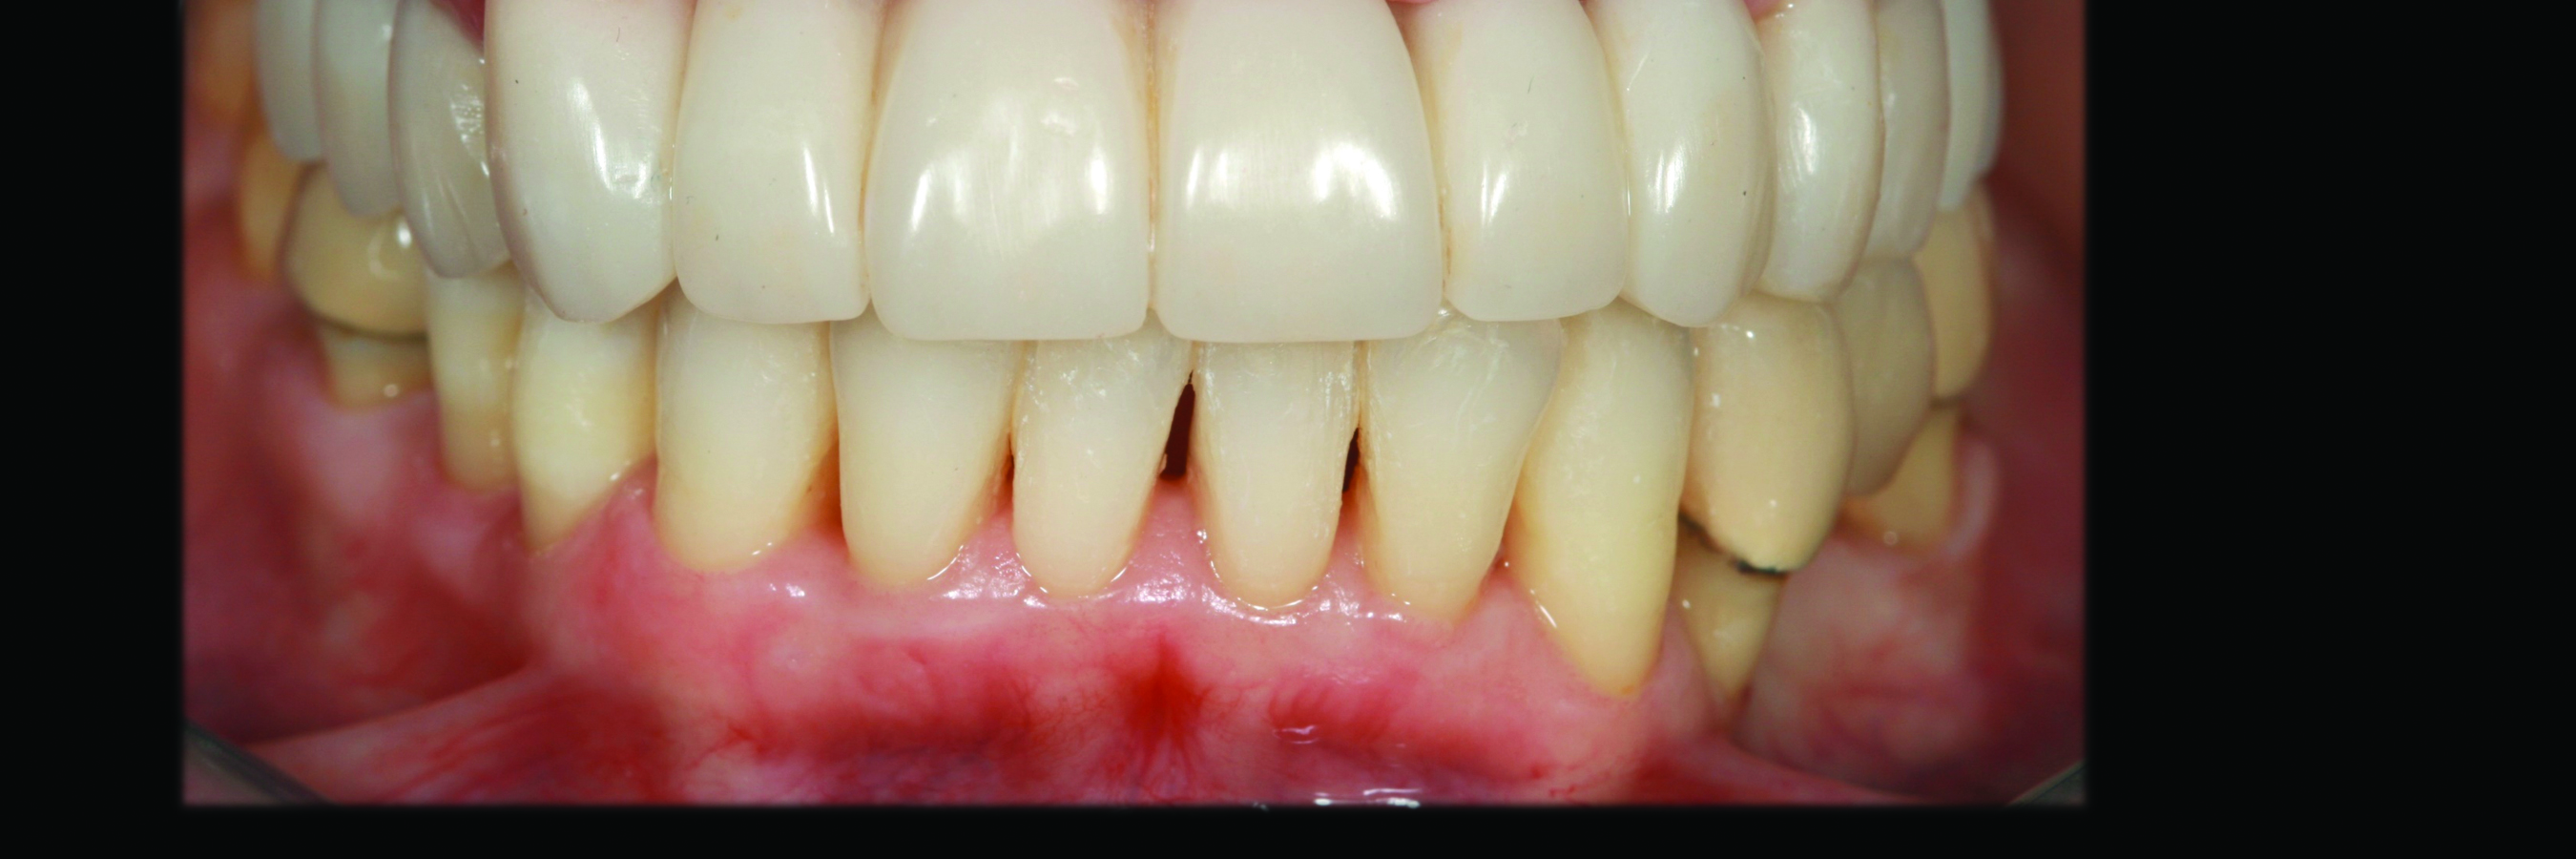

Fig 4. Case 1. Initial presentation of a patient with periodontitis (teeth Nos. 22 through 27). Generalized pocket depths of 5 mm to 6 mm were present.

Figure 4

Fig 6. Results of SRP demonstrated resolution of inflammation and residual probing depths of 2 mm to 3 mm, 18 years after treatment of Case 1 patient.

Figure 6